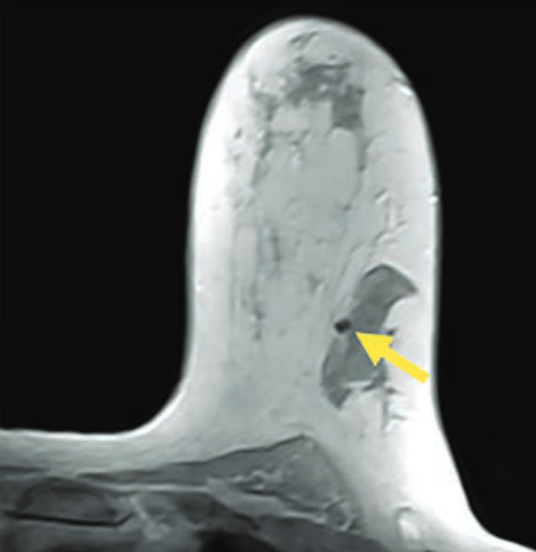

La séquence IRM Dixon en phase testée pour l’étude des zones de présence d’un clip de biopsie mammaire

Cette étude rétrospective du Dr Taylor-Cho et de son équipe a porté sur 164 femmes (âge moyen, 50,3 ans) avec un total de 281 clips de biopsie mammaire qui ont subi une IRM mammaire injecté entre le 2 janvier 2019 et le 16 avril 2020. Sans être informés de l’identité de des patientes, sur la séquence utilisée ou sur les détails du clip de biopsie, trois radiologues ont annoté indépendamment leurs résultats sur trois séquences cliniques - pondérée en T1 (T1W) sans suppression de graisse (NFS), STIR, première phase de contraste dynamique T1W avec suppression de graisse (FS ) — ainsi que Dixon en phase. La confiance a ensuite été enregistrée sur une échelle de 1 à 4.

Au final, les chercheurs ont constaté que, par rapport aux séquences T1W NSF, STIR et T1WFS, la séquence Dixon en phase injectée a mis en évidence la sensibilité la plus élevée pour la détection des clips de biopsie mammaire (85,1 % contre 26,6 % -78,2 %), la plus grande confiance des lecteurs (3,5 contre 1,7 à 3,0) et le rapport signal/bruit le plus élevé (4,05 contre 0,54 à 1,21), sans différence significative de valeur prédictive positive (96,4 % contre 92,2 % à 96,1 %).